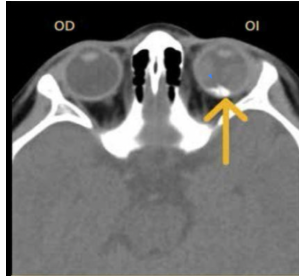

Hallazgos que podemos encontrar en una TC de orbitopatía tiroidea

Agrandamiento de los músculos extraoculares

Áreas de baja densidad debido a depósitos de glucosaminoglicano

Exoftalmos

Nervio óptico estirado

¿Qué características esperas encontrar en una RM en secuencia T1 en la enfermedad de orbitopatía tiroidea?

Agrandamiento de músculos extraoculares

¿Qué características esperas encontrar en una RM en secuencia T2 en la enfermedad de orbitopatía tiroidea?

Aumento de señal en músculos extraoculares en fase agudas

Diámetro disminuido del nervio óptico